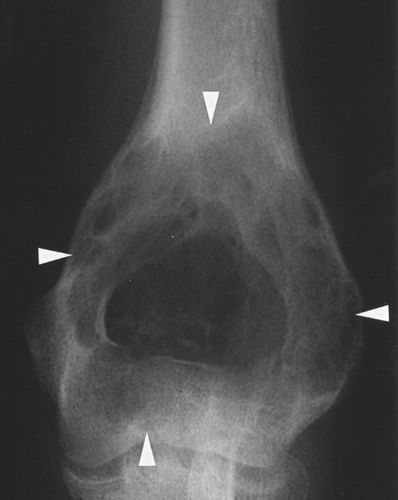

动脉瘤样骨囊肿是溶骨性的,通常是扩张的病变,最常见于长骨的干骺端。它们出现在较年轻的一组(通常在5至20岁之间),在年龄上与巨细胞瘤重叠较小。如果囊肿在骨膜闭合后发生或持续存在,那么它可能延伸到骨骺并且与巨细胞瘤无法区分(图9A)。CT或MRI可显示液体水平,代表血液分层(图9B)。缺乏增强固体成分也将支持巨细胞瘤与动脉瘤样骨囊肿的鉴别。

图9A-13岁女孩,动脉瘤样骨囊肿。照片显示肱骨远端近关节面的轻微可扩张的病变(箭头)。